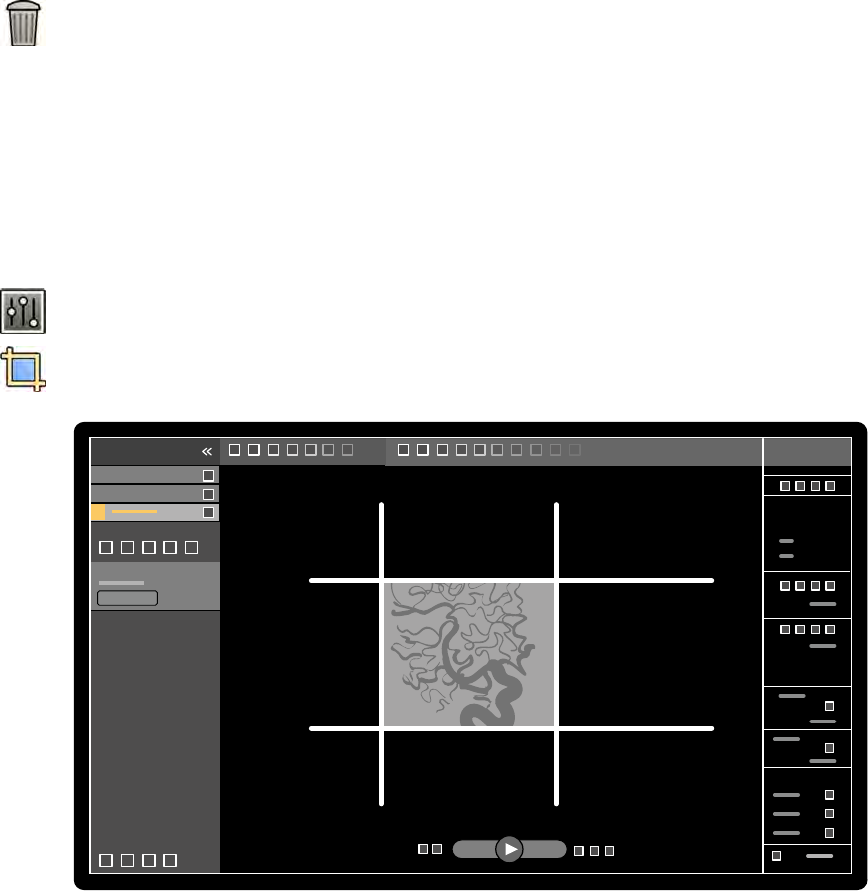

18.1 WorkSpot..............................................................................................................................342

18.1.1 Monitor akwizycji.................................................................................................342

18.1.2 Monitor do przeglądania......................................................................................344

18.2 FlexSpot (opcja)....................................................................................................................346

18.2.1 Główny monitor FlexSpot.....................................................................................346

18.2.2 Dodatkowy monitor FlexSpot...............................................................................347

18.2.3 Dodatkowy system FlexSpot................................................................................ 347

18.3 FlexVision (opcja)................................................................................................................. 347

18.4 Moduł ekranu dotykowego.................................................................................................. 348

18.6 Paski narzędzi....................................................................................................................... 353

18.7 Narzędzia ogólne.................................................................................................................. 354

18.8 Moduł sterujący................................................................................................................... 355

18.9 Moduł przeglądowy..............................................................................................................357